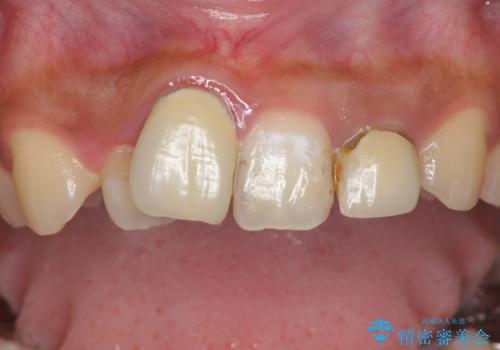

銀歯を白く 虫歯治療

- 虫歯治療を希望して来院。

保険適用の銀色のつめもののやり替えを行いました。

- 30.8万円(右上4567 emaxプレスインレー 7万円x4本)費用は治療当時の料金となります

自由診療のインレーの歯型には、シリコンを使用しています。また、処置時には8倍の拡大鏡を用いて、精密に治療しております。